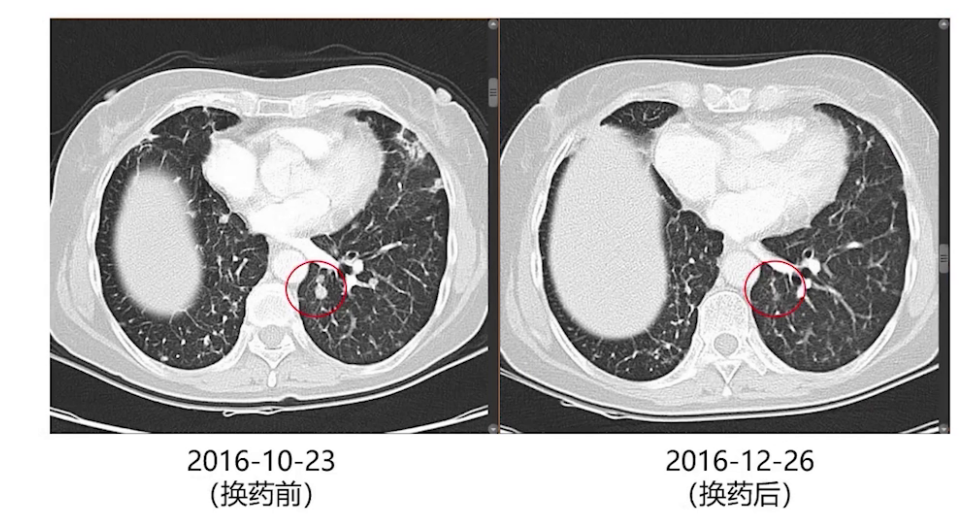

2018年9月发现左肺上叶新增结节并逐渐增大,2021年1月全身评估后,考虑患者处于寡进展状态,2月行胸腔镜下左肺上叶楔形切除术,切除增大结节。术后病理提示肺组织中可见中低分化腺癌,浸润肿瘤最大径1.2cm,送检NGS检测提示EGFR exon19缺失突变、EGFR exon20的T790M突变及MET基因扩增。术后继续奥西替尼靶向治疗。